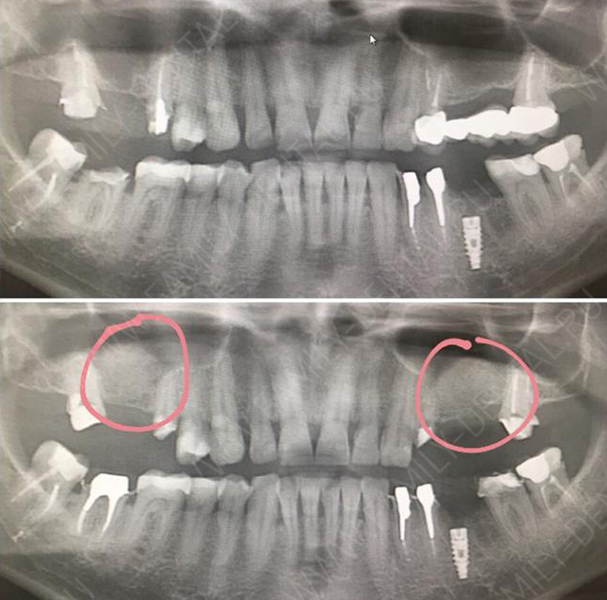

Исследование на рентгене после имплантации зубов

Раздел: Снимки-откровения